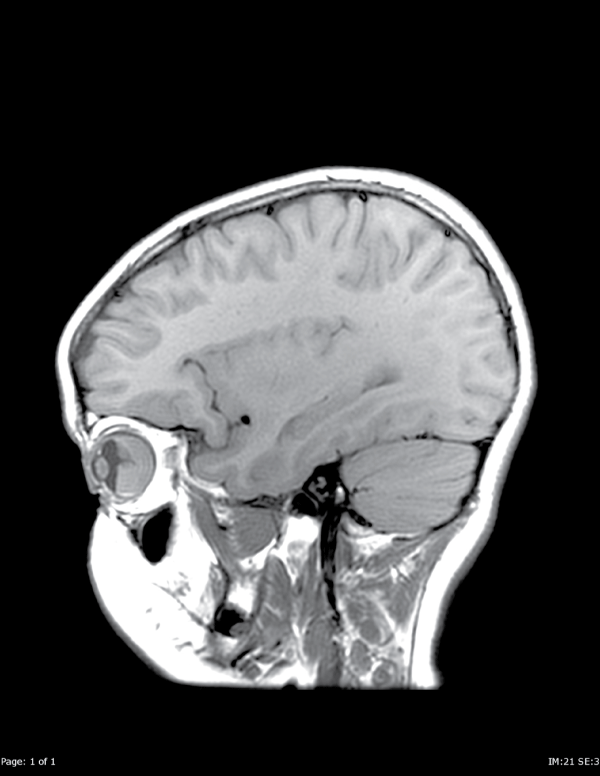

MRI of the orbit and brain with and without gadolinium contrast and with diffusion weighted imaging was obtained revealing retinal detachment with an underlying mass in her right eye. Given her history of leukemia as well as previous retinal hemorrhage, both of these possibilities were considered in the differential diagnosis. Other etiology considered in the differential included orbital cellulitis, dermoid cyst and other oncological process. Precontrast T1 weighted images demonstrated a mass in the posterior globe, which was uniformly T1-isointense to cerebral gray matter. However, post-gadolinium T1 weighted images and T2 weighted images demonstrated two components to the mass: an anterior T2-hyperintense, nonenhancing component, and a posterior T2-hypointense, enhancing component. Imaging characteristics of the anterior component were consistent with subretinal hematoma or proteinaceous exudate. Uniform enhancement identified the posterior component as solid tissue, rather than bland hematoma. The posterior component of the lesion demonstrated uniform restricted diffusion (ADC=6.3×10e-4 mm2/s), suggesting dense cellularity as in a leukemic infiltrate (Figure A1, A2, B1, B2).

Figure A1: Sagittal T1 pre-contrast images demonstrate a mass in the posterior right globe.